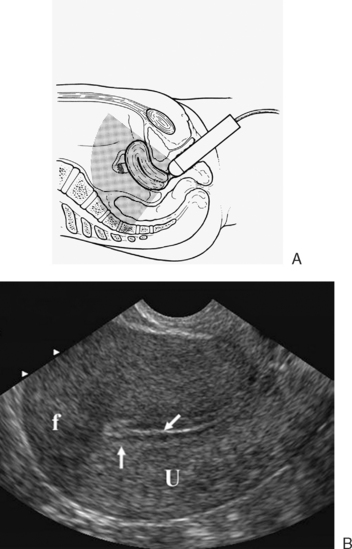

Caveat: Standard transvaginal ultrasound often can’t definitively diagnose tube blockade. Let’s unpack.

A transvaginal ultrasound might detect a hydrosalpinx — a fluid-filled, dilated tube. But if the tube is blocked yet not dilated, ultrasound may miss it.

There are specialised ultrasound procedures called Sonosalpingography or HSSG/HyCoSy (contrast fluid or foam introduced to assess flow) that help evaluate tubal patency without the radiation of a traditional X-ray.

A dilated tube filled with fluid (hydrosalpinx) appearing as a sausage-shaped or tubular anechoic structure.